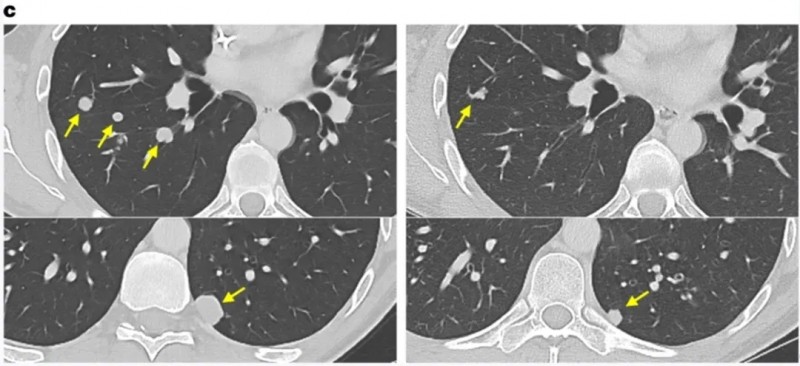

值得一提的是,S-01号患者的治疗效果尤为突出,该患者在接种疫苗后至少达到病情稳定(SD),对比接种DC疫苗前的CT影像(左图)与接种后的影像(右图),可见其左主动脉旁淋巴结出现退化(详见下图)。

▲图源“Oncoimmunology”,版权归原作者所有,如无意中侵犯了知识产权,请联系我们删除